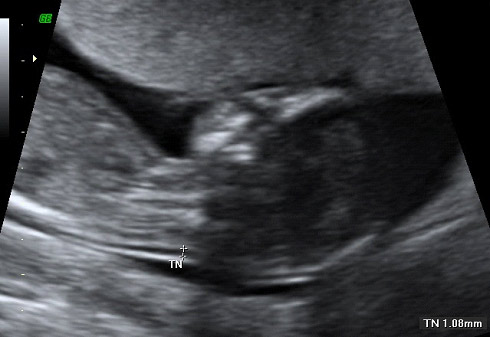

La medida del pliegue nucal (técnicamente llamado translucencia nucal) se considera un marcador de alteraciones genéticas como el síndrome de Down o el Turner, y es la zona que queda por detrás del cuello del feto. Cuando el grosor es mayor de la media normal (generalmente en torno a los 3 milímetros en la semana 12) puede existir mayor riesgo de que se asocie a un feto con síndrome de Down y por tanto, recomendarse la realización de una amniocentesis a partir de la semana 15 de embarazo o una biopsia corial en ese momento para confirmar el diagnóstico.

Feto de 12 semanas con medición del ductos venoso

El ductos venoso es la comunicación entre la vena umbilical y el corazón y en esta imagen vemos el corte longitudinal en un feto de 12 semanas. Se trata de un marcador ecográfico de aneuplodía (anomalía cromosómica) en la semana 12 de embarazo, ya que un 80% de los fetos con trisomía 21 (síndrome de Down) tienen un flujo anormal en el ductos venoso.